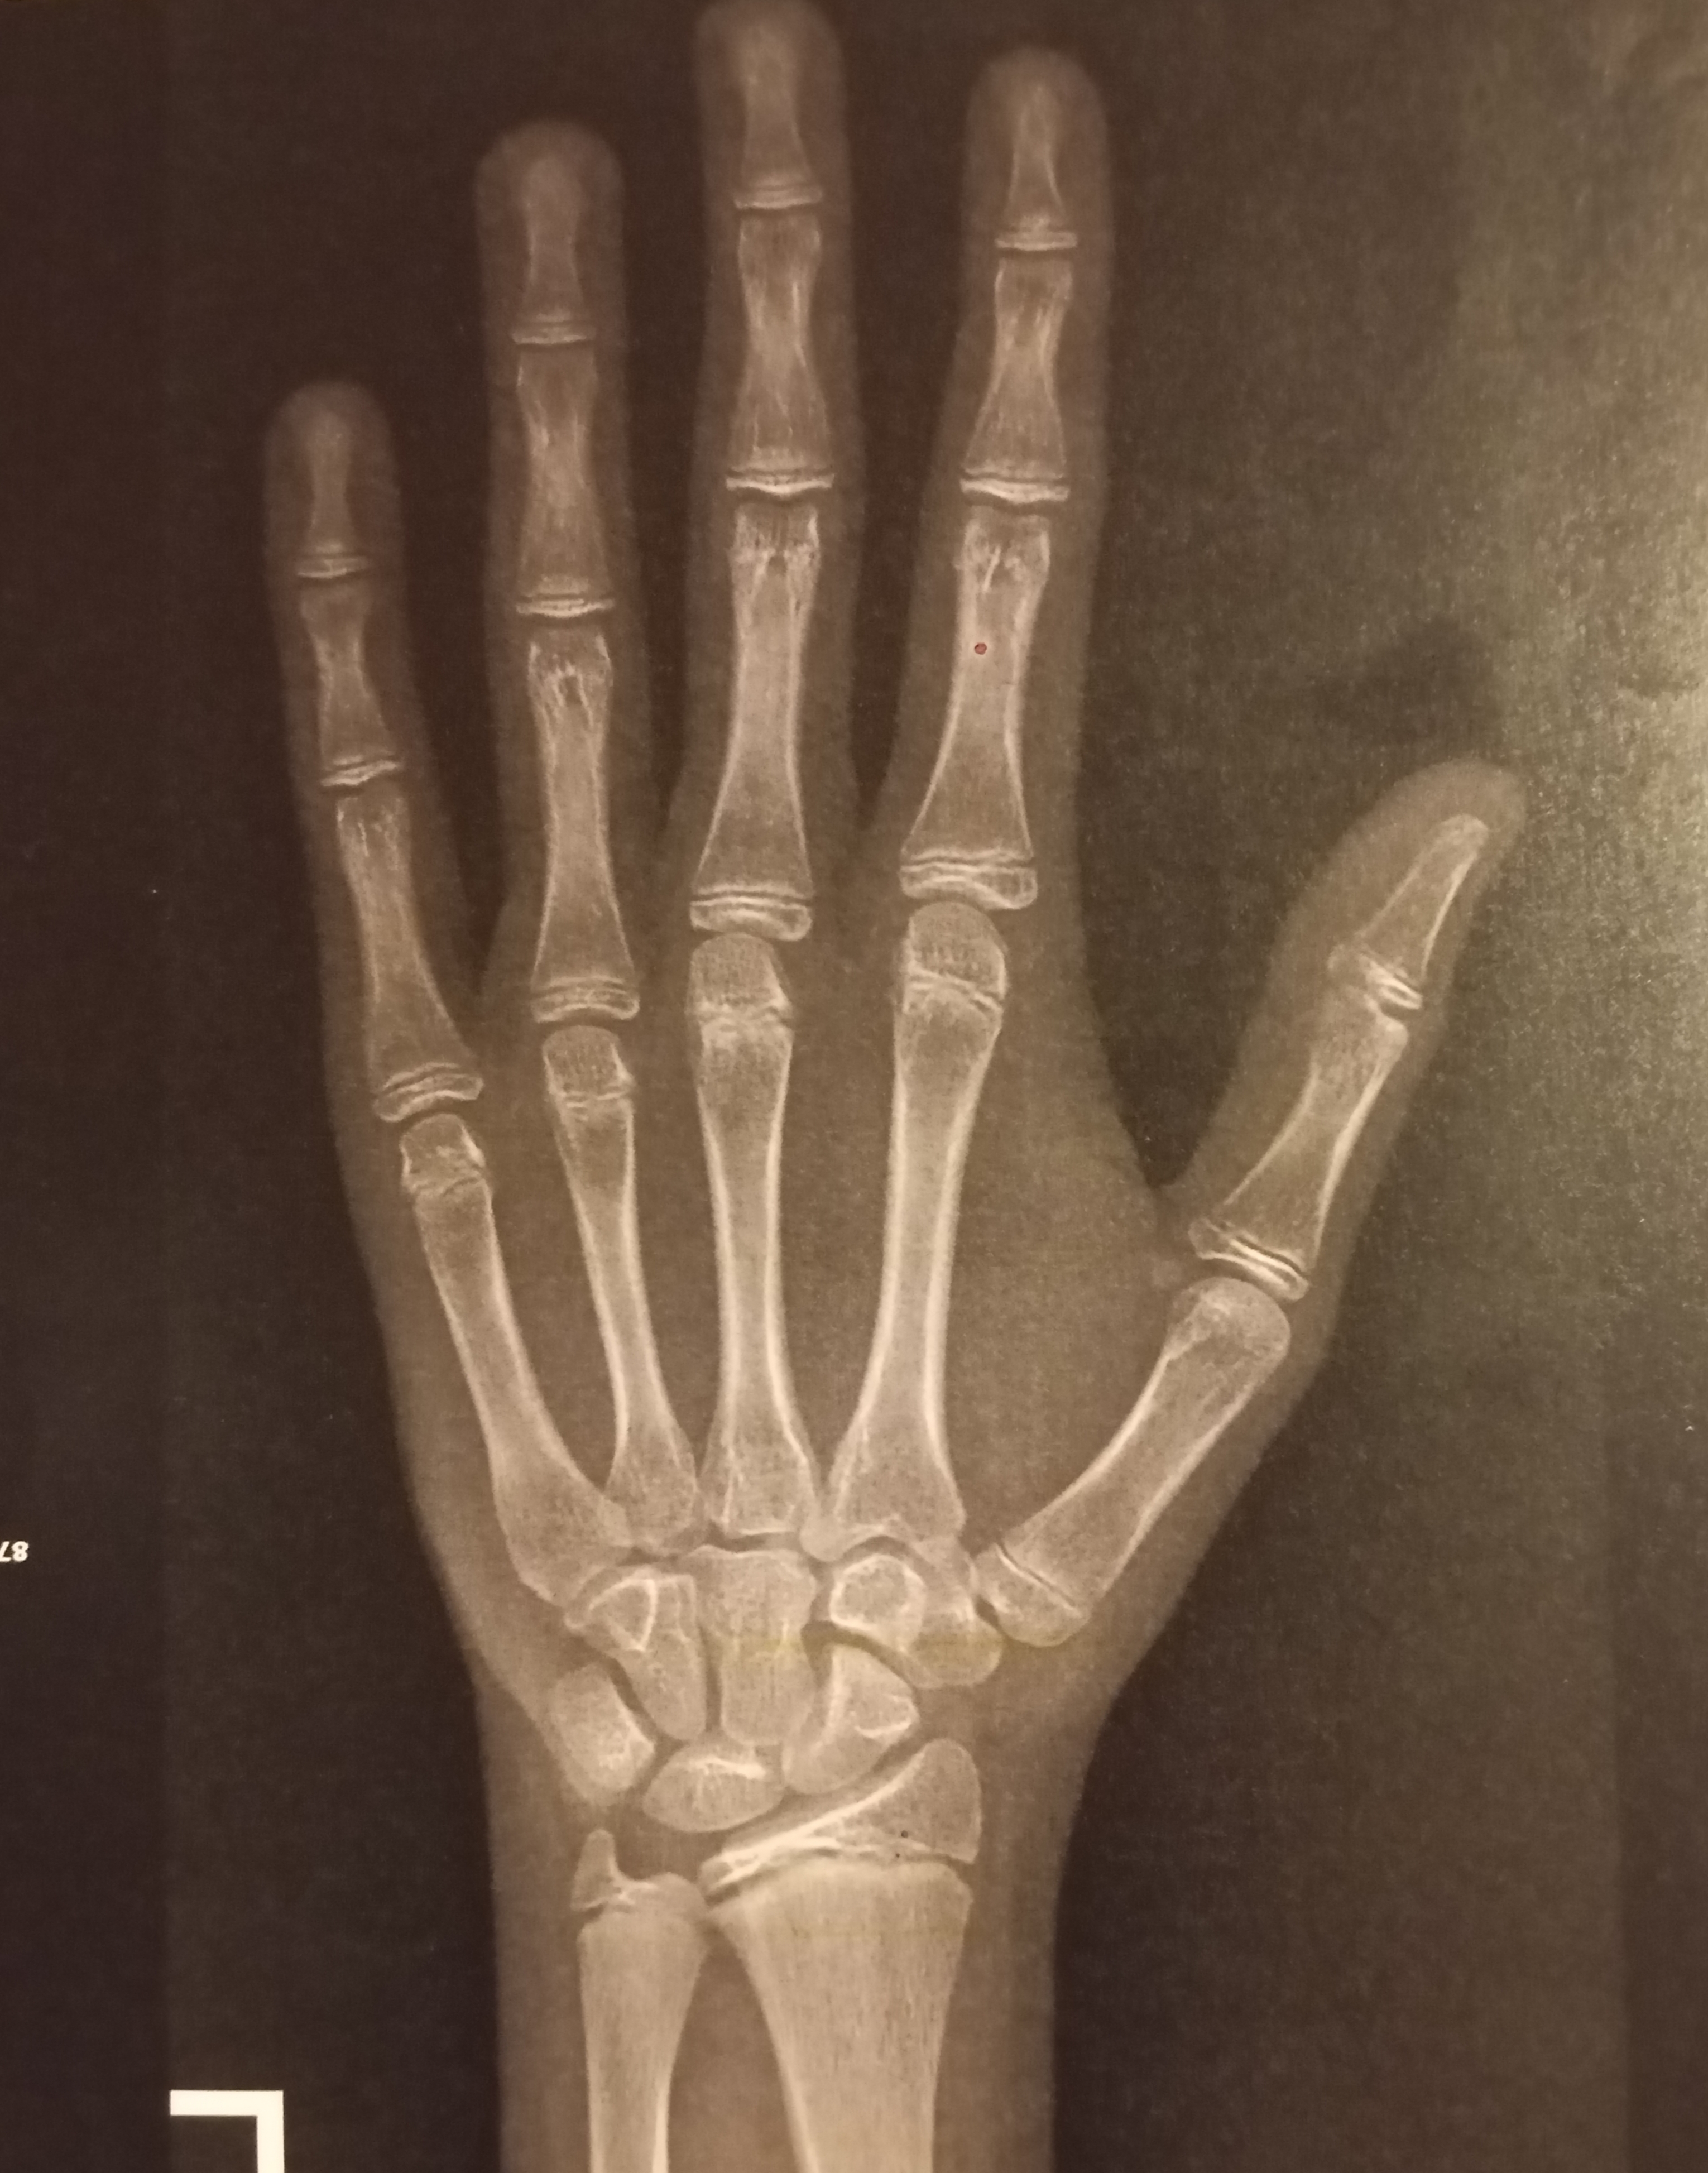

im 16 and 5'6, my mom is 5'9 and my dad 5'11

Doctor said my growth plates have already "matured" which doesn't make sense to me. From what i can see my body age goes around 14, still in puberty.